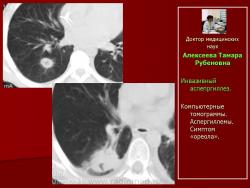

Другой оппортунистический микоз – аспергиллез, вызванныйплесневыми грибами Aspergillusspp., установлен в 14,3% (12 наблюдений). При инвазивном аспергиллезе рентгенологически нами выделено 2 формы поражения легочной ткани: полостная в 91,7% случаев и диссеминированная в 8,3%.

При полостной форме инвазивного аспергиллеза определялись разнокалиберные (от 0,8 - 4,5см. диаметром) единичные (рис. 18, 19) или множественные полостные образования, связанные с сосудами, имеющие пристеночные шаровидные массы внутри, окруженные полумесяцем. Отмечалось неравномерное утолщение стенок полостей на ограниченном участке или по всему периметру (рис. 20). Иногда вокруг полостных образований выявлялся симптом «ореола» вокруг и реакция прилежащих отделов плевры.

Рис.18. Б-ной Г. Лимфома Ходжкина. Инвазивный аспепргиллез.

Компьютерные томограммы. Аспергиллема.

Рис. 19. А. Б-ной К. НХЛ. и Б. Б-ной В. НХЛ. Инвазивный аспепргиллез.

Компьютерные томограммы. Аспергиллемы. Симптом «ореола».

Рис. 20.Б-ной Т. Лимфома Ходжкина

Компьютерные томограммы Множественные полостные образования с массой мицелия внутри.

Следует отметить, что во всех наблюдениях полостные образования – аспергиллемы появлялись в неизмененной ранее легочной ткани.

Независимо от формы поражения нами отмечено, что при инвазивном аспергиллезе информативным признаком являлось наличие полостных образований.

Для другого оппортунистического микоза - аспергиллеза легких наиболее информативным рентгенологическим признаком являлось наличие полостных образований.Разнокалиберные (0,8 - 4,5см. диаметром) единичные или множественные полостные образования с пристеночными шаровидными массами внутри, окруженные полумесяцем и «ореолом» вокруг, развивались в неизмененной легочной ткани. Стенки полостей были неравномерно утолщены на ограниченном участке или по всему периметру. В ряде случаев имела местореакция прилежащей плевры.